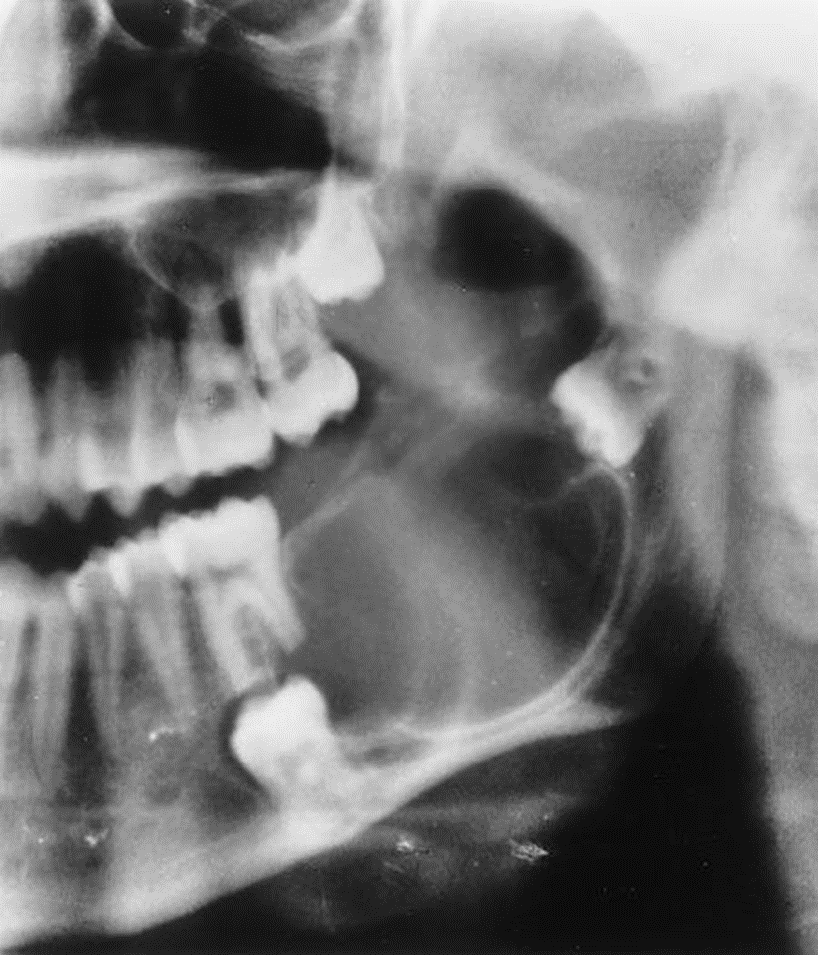

3. This is a 35-year-old asymptomatic woman who has slight buccal and palatal enlargement of the alveolar bone in this area. Other studies indicated portions of the zygoma were involved. This condition was first detected at age 19 years and is slowly progressive. Her alkaline phosphatase was normal to high-normal, and her serum calcium was normal.

What is your diagnostic impression?